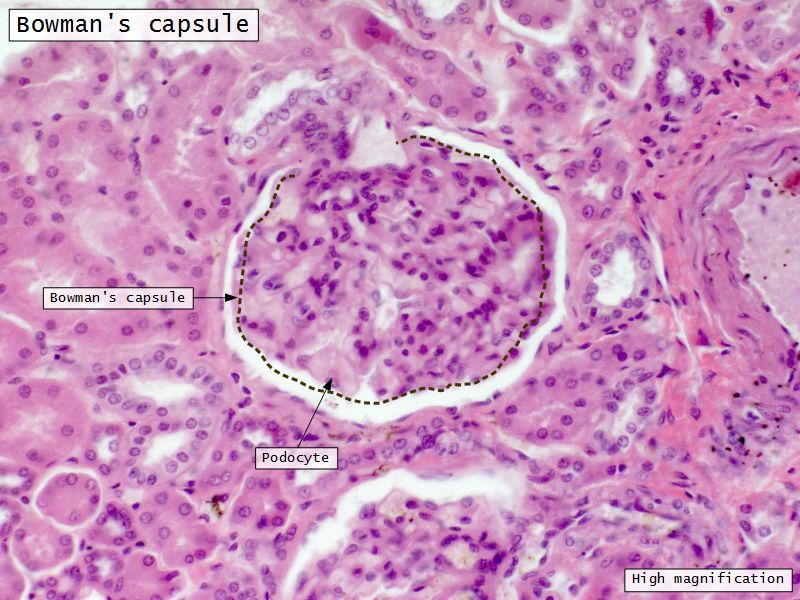

Renal corpuscle

- Tuft of capillaries

- grow into

- Blind end of nephron

- Several layers of epithelium

- Two sides

- Vascular pole

- Tubular pole

Epithelium layers

- Capillary endothelium

- Visceral layer of epithelium

- Podocytes

- Resting on glomerular basement membrane

- Capsular space

- Parietal layer of epithelium

- Simple squamous epithelium

Podocytes

- Visceral layer of epithelium

- Protrude into capsular space

- Attached to basement membrane

- Long cytoplasmic extensions

- Primary processes

- Secondary processes

- Podocyte feet

- Tightly spaced

- Filtration slits 20 - 30 nm wide